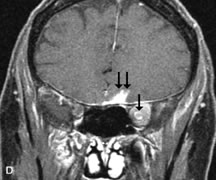

PATIENT PREPARATION Before MRI is performed, patients must be screened and prepared to avoid the potential hazards associated with the strong magnetic field. Patients who have ferrous aneurysm clips or cardiac pacemakers, who depend on life-support equipment, or who retain a possible metallic intraocular foreign body are not candidates for this imaging modality. MRI cannot be performed on obese patients who cannot fit into the bore of the magnet. Patients who are claustrophobic may not tolerate a prolonged period of study within the confines of the magnet, whereas others might do well if given a mild sedative. All worn metallic objects (e.g., necklaces, watches) should be taken off, credit cards set aside, and eye makeup removed before entering the room containing the magnet.5,20,34,35,36 NORMAL ORBITAL ANATOMY T1-weighted images provide the best anatomic details of the orbit because they display superior contrast resolution between normal structures (see Fig. 8). The vitreous has a long T1, resulting in an intermediate signal similar to brain, whereas the crystalline lens and sclera appear dark because of a longer T1 and short T2. The extraocular muscles, like all skeletal muscles, demonstrate a moderately long T1 and short T2 and highly contrast with the intense signal of the surrounding orbital fat (adipose tissue has an extremely short T1). The lacrimal glands appear as mottled areas of reduced intensity of the signal from the orbital fat in the lacrimal fossa. The optic nerves are seen with the same signal intensity as brain white matter and are hypointense relative to the orbital fat because their Tl is longer than the Tl of fat but shorter than the Tl of water. Cortical bone is not well delineated because it contains little free water, yielding minimal signal in MRI, and thus appears dark on all pulse sequences. This feature explains why MR images of the orbital apex and intracanalicular portion of the optic nerves are superior to comparable CT scans. Partial volume averaging of the bones in these regions obscures soft tissue details on CT images, whereas MRI reveals the signals only from the soft tissue structures with no cortical bone input. Bone marrow, on the other hand, is seen as a relatively intense signal because of its high fat content (see Fig. 8).37,38 T2-weighted pulse sequences are not ideal for imaging normal anatomy; however, they are particularly useful in revealing pathologic conditions (see Fig. 9). T2-weighted studies are most easily recognized by a bright vitreous signal. ORBITAL DISEASES Vascular Lesions Cavernous hemangiomas appear as well-circumscribed, smooth, usually intraconal masses that are isointense to muscle on T1-weighted images and hyperintense on T2-weighted images (Fig. 12). Patchy early enhancement is typically followed by diffuse, more homogeneous enhancement.39 The internal architecture of the mass, including septation and internal vasculature, may often be appreciated with high-quality orbital imaging.40 Lymphangiomas consist of ectatic vascular channels within a connective tissue stoma with varying degrees of lymphoid cellularity. On MRI, these tumors are typically poorly circumscribed, multicompartmental, and heterogeneous, often showing cystic dilations with fluid levels (Fig. 13). The signal characteristics within lymphangiomas vary considerably, reflecting cystic and solid components and the varying paramagnetic characteristics of blood at different stages of degradation.40–42 Acute hemorrhage appears hypointense on both T1- and T2-weighted formats. Methemoglobin present in subacute hemorrhage (3 to 14 days) leads to hyperintense signal on both T1- and T2-weighted images.41 A small percentage of lymphangiomas appear radiologically indistinct from orbital cavernous hemangiomas.43 Orbital varices are venous malformations that expand with increased systemic venous pressure, such as with Valsalva maneuvers. Because rapid acquisition of images during a Valsalva maneuver is important in imaging such a lesion, conventional or spiral CT is currently the modality of choice.44 MRI is an excellent modality for demonstrating enlargement of the cavernous sinus and dilation of the superior ophthalmic vein in patients with high-flow carotid-cavernous fistulas (Fig. 14).37MRA may be helpful in the evaluation of the venous outflow pattern. The rapidly flowing blood in these vascular structures carries the excited protons out of the section before they can be imaged, resulting in their dark appearance.5 In low-flow dural arteriovenous malformations, MRA may help define the arterial feeding vessels.45 Neural Lesions MRI is more effective than CT in delineating the intracranial optic nerves, chiasm, and optic tracts and, for this reason, is the preferred imaging modality in the evaluation of optic nerve disorders. The spatial relationships and image contrast of the orbital tissues with intraorbital optic nerve tumors is comparable between the two imaging modalities. The normal nerve is isointense to brain and appears enlarged and kinked owing to infiltration of an optic nerve glioma on T1-weighted images. Gliomas appear hyperintense on T2-weighted images and may be heterogeneous owing to cystic areas within the tumor. Contrast enhancement is variable.46 Intraorbital and intracranial optic nerve sheath meningiomas are usually isointense to cortical gray matter on Tl-weighted images and remain isointense on proton density studies (Fig. 15). Gd-DTPA is useful in delineating the intracranial extension of optic nerve meningiomas.7,47 The hyperostosis of bone and calcification associated with meningiomas are not demonstrated as well on MRI studies as on CT scans.20,37 Gd-DTPA–enhanced MRI also appears promising in the study of the permeability of the blood–brain barrier in selected optic neuropathies.22,48 MRI may reveal an enlarged optic nerve and some degree of contrast enhancement in cases of optic neuritis.49 Muscle Disorders Extraocular muscle enlargement in patients with thyroid-associated orbitopathy is demonstrated equally well with CT and MRI studies. However, the superior tissue contrast on MR images reveals better details of the relationships of the optic nerve to the thickened muscles at the orbital apex (Fig. 16).50 In addition, MRI may be able to differentiate between muscles that are enlarged as a result of edema and active inflammation and those enlarged because of fibrosis by their T2 relaxation times.21 Quantitative MRI was not found to be accurate in predicting the success of low-dose orbital irradiation.51 However, a muscular index relating the diameters of the rectus muscles to the bony orbital dimensions was useful in predicting optic nerve compression.52 MRI is also effective in imaging orbital tumors of mesenchymal origin, such as rhabdomyosarcoma, particularly in the assessment of extension into the anterior and middle cranial fossae (Fig. 17).37 The lack of any pathognomonic radiologic features necessitates rapid orbital biopsy when rhabdomyosarcoma is suspected. Osseous Lesions In general, CT is the imaging modality of choice when details of quantity and quality of bone are needed; however, abnormalities of bones can be detected indirectly by MRI. Cortical bone appears black (signal void) on MR images because of its low proton density and free-water content. The absence or discontinuity of the signal void of the orbital walls may represent bony destruction or fracture. Hyperostosis associated with prostate metastases or meningioma is visualized as areas of black smudging.50,53 Diseases in which the bone is replaced by pathologic tissues with a high free-water content, such as fibrous dysplasia, are well demonstrated on MRI. An intermediate signal intensity on T1-weighted images and hypointense signal on T2-weighted images is representative of fibrous dysplasia. Enhancement on post–Gd-DTPA MR scans is seen and is more evident in areas that are less mineralized.54 Cystic Lesions Dermoid cysts appear as rounded, well-defined lesions typically contiguous with an orbital bony suture. The high-intensity signal on T1-weighted images is attributed to the sebaceous-produced lipid contents (Fig. 18).31,50 Mucoceles may demonstrate a hypointense or hyperintense signal on MR images, depending on the concentration of proteinaceous or inflammatory fluid components. The integrity of the bony walls of the expanded sinus cavities cannot be assessed on MR as well as by CT.37,50,55,56 A high-signal intensity on Tl- and T2-weighted images is characteristic of orbital chronic hematic cysts because of the blood-breakdown products within the cysts.57 Trauma Although soft tissue relationships are usually better demonstrated on MRI, the evaluation of craniofacial bony trauma is preferable with CT. For example, prolapse of orbital fat through a fracture site and hemorrhage of adjacent tissues are demonstrated in an MR image, but the actual fractured bone is not imaged. Three-dimensional MRI of the orbit in subacute trauma has been described,58 although its precise role is not currently established. MRI has been suggested to be superior to CT in detecting intraorbital wooden foreign bodies.59,60 In a series of penetrating orbital injuries with organic foreign bodies, however, MRI was able to identify the foreign body in only four of seven cases.61 With an in vitro model for wood foreign body, McGuckin and colleagues concluded that CT was the imaging modality of choice.62 A careful history and, in selected cases, plain films to rule out a metallic foreign body are crucial before MRI is considered in patients with periocular trauma. MRI is particularly helpful in the detection and characterization of subperiosteal hematomas of the orbit (Fig. 19). They are most commonly seen in the subperiosteal space of the superior orbit as well-defined masses following a traumatic injury. The signal intensity varies depending on the acute, subacute, or chronic nature of the hematoma, based on the stage of blood degradation. Fresh hemorrhages are hypointense on T1-weighted images and hyperintense on T2 images. Hematomas that are 1 to 7 days old are hypointense on both T1- and T2-weighted images. T1-weighted images of hematomas more than a week old are hyperintense due to the oxidation of deoxyhemoglobin to methemoglobin, whereas the T2 images remain hypointense.63 Metastatic Tumors Breast carcinoma metastatic to the orbit has been demonstrated to be hypointense to the surrounding orbital fat on T1-weighted studies and hyperintense on T2-weighted images and has an affinity to the extraocular muscles (Fig. 20).50,64 The MRI characteristics of prostate carcinoma metastatic to the orbit have been described as involving the greater and lesser wing of the sphenoid, orbital roof, and optic canal. Diffuse bone hypertrophy with isointense or slightly hyperintense tissue on T1-weighted images represents the osteoblastic carcinomatous bone infiltration. Contrast enhancement is variable on T1-weighted and fat-suppressed images.65 Most other metastatic tumors also have a lower intensity signal on T1-weighted images and appear to displace or infiltrate normal orbital structures; however, their signal characteristics are variable on T2-weighted MR images.66 Many metastatic tumors demonstrate bright contrast enhancement with Gd-DTPA. Infectious Disorders MRI findings of preseptal and orbital cellulitis typically include increased signal intensities on T2-weighted images of the eyelids and orbital fat, respectively, due to the increased water content of the tissues. Since most cases of bacterial orbital cellulitis are associated with paranasal sinusitis, hyperintense signals of the affected sinuses may also be found on T2-weighted images as well as enhancement of polyps and granulation tissue on postgadolinium T1-weighted MR images. Subperiosteal abscess formation may occur due to contiguous spread of infection from the paranasal sinuses and appear on MRI as an area of intermediate signal on T1-weighted and proton-weighted MR images. The abscess may appear slightly hyperintense compared with muscle on T2-weighted scans with the necrotic contents having the greatest intensity.67 MRI and MRV are more sensitive than CT in revealing cavernous sinus thrombosis. Engorgement of the cavernous sinus, extraocular muscles, and ophthalmic veins is seen with hyperintensity of the thrombosed sinuses evident on all pulse sequences. The enlarged, thrombosed superior ophthalmic vein appears less hypointense than the normal contralateral ophthalmic vein, and hyperintensity within the lumen of the vessel may be seen on T1- and T2-weighted MR images.68 Inflammatory and Lymphoproliferative Lesions Inflammatory conditions of the orbit, both idiopathic (inflammatory pseudotumor) and those of known causes, have been found to be hypointense to fat and isointense to muscle on Tl-weighted studies and isointense or slightly hyperintense to fat on T2-weighted images (Fig. 21).50,64,69 The more fibrous or sclerosing varieties have less signal intensity on T2-weighted images. Marked enhancement is seen in pseudotumor infiltrates after gadolinium administration.70 The same signal characteristics are demonstrated in patients with Tolosa-Hunt syndrome, with mass lesions seen in the cavernous sinuses and orbital apices.71 Lymphomas have MRI characteristics similar to those of inflammatory lesions in that they are hypointense to fat and isointense to muscle on T1-weighted images (Fig. 22). They may appear hyperintense to fat on T2-weighted images, perhaps owing to less fibrosis than that seen in orbital inflammatory pseudotumor, although this is not a consistent finding.31,50,66 Lymphoid tumors typically enhance moderately after contrast injection. Unfortunately, studies have shown that tumor density and homogeneity are similar between inflammatory and malignant orbital infiltrates, and MRI cannot differentiate these lesions.72,73 Lacrimal Gland Tumors Lacrimal gland lesions present special problems in diagnosis and management. Pleomorphic adenoma (benign mixed tumor) should not be biopsied, but rather excised in toto. On the other hand, for lymphoma and inflammatory infiltrates, incisional biopsy is more appropriate than complete excision of the lacrimal gland. Thus, preoperative clinical and radiologic evaluation are especially crucial in planning appropriate surgical management. Pleomorphic adenomas demonstrate long T1 and T2 signal characteristics. They may show heterogeneity on T2-weighted images74 and moderate to marked enhancement with contrast.75 Signal characteristics of adenoid cystic carcinoma include hypointensity to fat on T1-weighted images, hyperintensity to fat with increased T2 weighting, and isointensity to fat on proton density-weighted studies (Fig. 23).31,75 Secondary bony alterations of the lacrimal fossa associated with lacrimal gland tumors, such as remodeling (benign mixed tumor) or destruction (adenoid cystic carcinoma), are seen indirectly on MR images; however, bone windows on CT scans provide better delineation of these changes. In contrast to the round or globular appearance of benign or malignant epithelial tumors of the lacrimal gland, lymphoproliferative tumors usually appear to be molding or draping onto the globe and the surrounding bony orbit. LACRIMAL DRAINAGE SYSTEM DISORDERS MRI with surface coils provides excellent spatial resolution and tissue-specific signal intensities of the lacrimal drainage system. These parameters have been found useful to more accurately demonstrate the extent of lesions in the lacrimal sac and differentiate long-standing mucoceles from solid tumors than CT.76 Physiologic studies in patients with tearing disorders now include MR dacryocystography, in which Gd-DTPA is either placed topically in the conjunctival fornix or injected by cannulation into the lacrimal sac. They provide a detailed morphologic and functional analysis of the lacrimal excretory system; however, they are no more sensitive than digital-subtraction dacryocystography or CT dacryocystography.77–79 INTRAOCULAR TUMORS On MRI, uveal melanomas have a typical appearance that helps to differentiate them from other primary and secondary intraocular tumors as well as choroidal detachments. Pigmented melanomas are hyperintense on Tl-weighted images, hypointense on T2-weighted studies, and hyperintense on proton density–weighted examinations (Fig. 24).30,31,50,80–82 These signal characteristics have been attributed to the paramagnetic properties of melanin because of stable free radicals that shorten the T1 and T2 relaxation times. Moderate enhancement is seen on postgadolinium T2-weighted images. Gadolinium-enhanced T1-weighted images are particularly sensitive in detecting choroidal melanomas.83 MRI may be less sensitive in detecting extrascleral extension of tumor than echography performed by an experienced ultrasonographer.84 Tumors metastatic to the choroid are hyperintense on T1- and T2-weighted images.24 The signal characteristics, however, may be similar to those seen with choroidal melanoma. Choroidal hemangiomas, on the other hand, have an intermediate signal on T1-weighted sequences and become hyperintense on T2-weighted images50 as well as proton density–weighted images.81 Retinoblastomas display moderate signal intensity on T1-weighted studies and a low signal on T2-weighted images.31,80,85 Calcification can be easily detected by CT and ocular ultrasonography but is not imaged by MRI.25,50 The presence of optic nerve involvement is best evaluated by MRI. ACQUIRED ANOPHTHALMIA When an eye is removed owing to tumor or trauma, an implant is typically placed in the intraconal space. MRI may be useful in defining the size, shape, and position of such orbital implants.86 Porous hydroxyapatite or polyethylene implants are preferred by many surgeons performing enucleation or evisceration. A porous implant offers the possibility of supporting a motility coupling peg to increase the movement of the overlying prosthesis. MRI with contrast is used by some surgeons to evaluate the degree of fibrovascular ingrowth in hydroxyapatite87 and porous polyethylene88 implants prior to motility peg placement. |